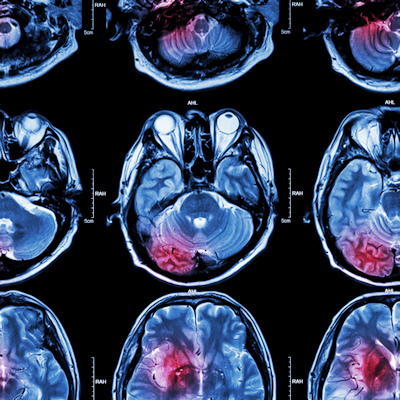

So why do us doctors put our patients through this experience? Not to be cruel, but to be kind. MRI is a modern marvel of medical technology that allows clinicians to peek inside the human body in exquisite detail without any of the side effects or risks of radiation exposure that come with x-ray or CT.

The human anatomy is largely water-based (hydrogen and oxygen atoms), and MRI capitalizes on that biochemical makeup by using hugely powerful magnetic gradients to control the orientation of every single hydrogen atom in the body, lining them all up in one uniform direction before releasing them and letting them spin away at frequencies only detectable by fine-tuned receivers. The physics behind it is complex yet astounding, and the images that result are quite simply breathtaking.